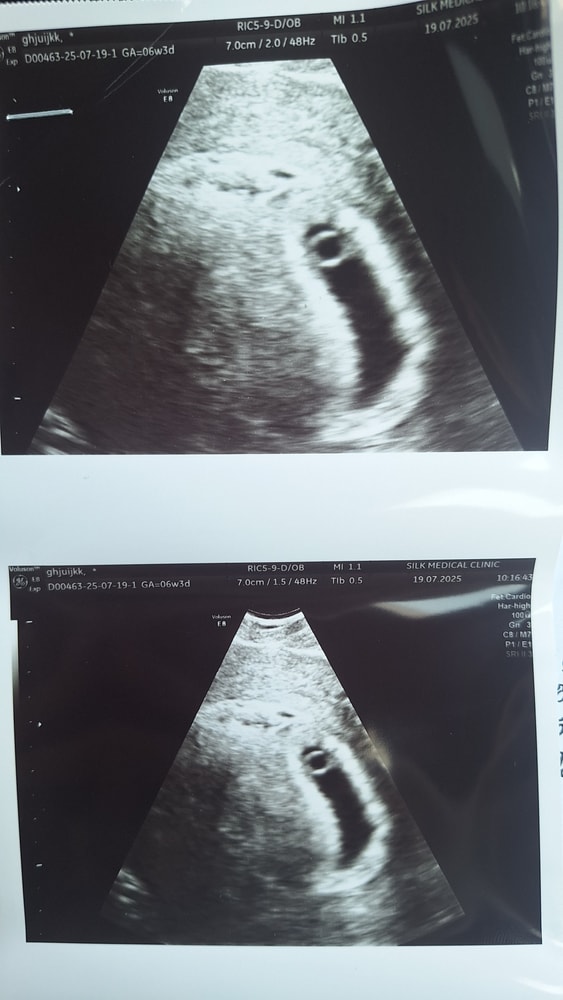

Нет еще сердцебиения 6 недель 4 дня

Беременность - 1 триместрБыла на узи, узистка мягко говорч попалась су....ка сказала что плодное яйцо деформировпнное срок 6.4 дня сердцебиение не прослушивается(сделала вагинальное узи)

НЕ могу сказать, что прогрессирует беременность но и замершей не назову.

У меня на сроке 6 недель 5 дней ни эмбриона не было, ни желточного мешка, поставили анэмбрионию по вопросом. Но плодное яйцо соответствовало сроку по размерам. Через неделю уже сердечко стучало.

Если еб и не знаете когда овуляция шанс есть. Если эко. То узист говорит верно. Данных за развитие нет. На этом сроке если он поставлен верно уже эмбрион от 5 мм и СБ+